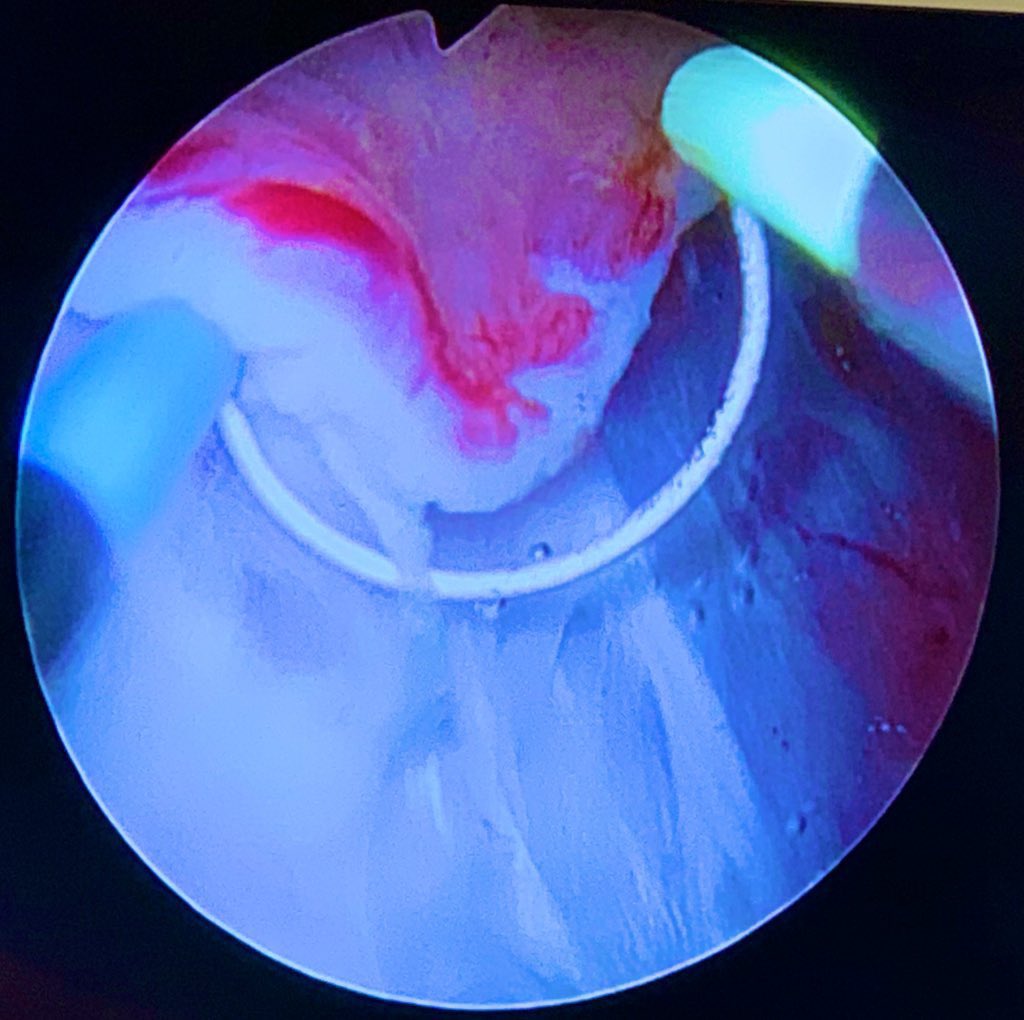

#enbloc#TURB#ERBC#NMIBC and the risk of obturator kick I feel safer to use loop and short energy “shots”#UroSoMe#uroczech#eauguidelines@jteoh_hkpic.twitter.com/cTuehbDuLf -

For

Dx. multicentric

#BladderTumor. Surgical hist. Previous#TURB#NMIBC. Qx.#EnBloc resection w/#Bipolar#Olympus. Thanks to@jteoh_hk for the opportunity to learn.#UroSoMe#BladderCancerpic.twitter.com/1iJjPdpIQX